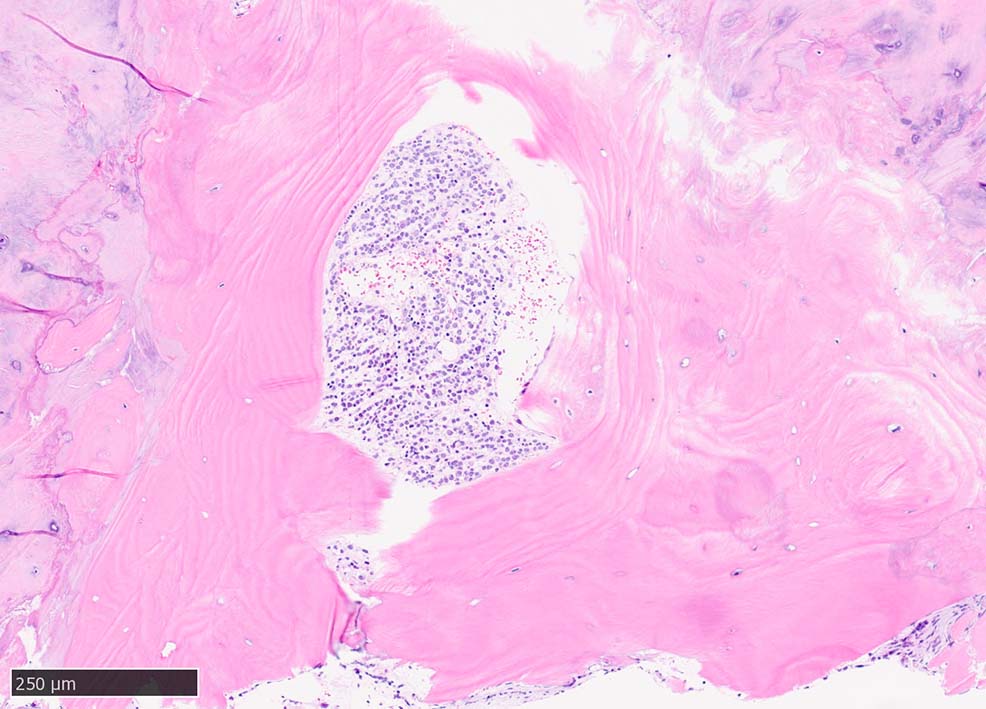

骨髄生検組織所見

骨髄生検組織では骨梁間に壊死に陥った細胞の凝固壊死像が確認できる. 本例では脂肪細胞は消失せず形態が残っている.壊死のあとには, 髄腔に線維化をきたす. 上図には線維化を示し, 右端の図では壊死巣と線維化の境界が観察される.

本例ではviableな腫瘍細胞がハーバース管と考えられる管内に認められた.(髄腔とハーバース管腔は解剖学的に同じ場所といえるのか?)

ハーバース管は緻密骨内の骨構造であり, 管内には動静脈, 脈管周囲リンパ管, 神経線維が入る. 解剖学的に海綿骨骨髄腔とは異なる空間構造と考えられる.--viableな腫瘍細胞の存在はリンパ管、血管内への腫瘍浸潤と考えられる.